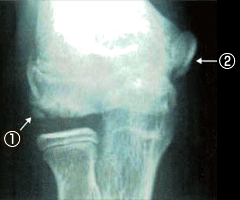

成長期にボールを投げすぎることによって生じる肘の障害を野球肘といいます。

上腕骨の外側、内側、後方の障害がありますが、内側の障害が約90%を占めると言われています。

肘の外側で骨同士がぶつかって骨・軟骨が剥がれたり痛んだりします。

また、肘の内側では靱帯・腱・軟骨がいたみます。

肘の後方でも骨・軟骨がいたみます。

X線(レントゲン)検査やMRI撮影で診断します。